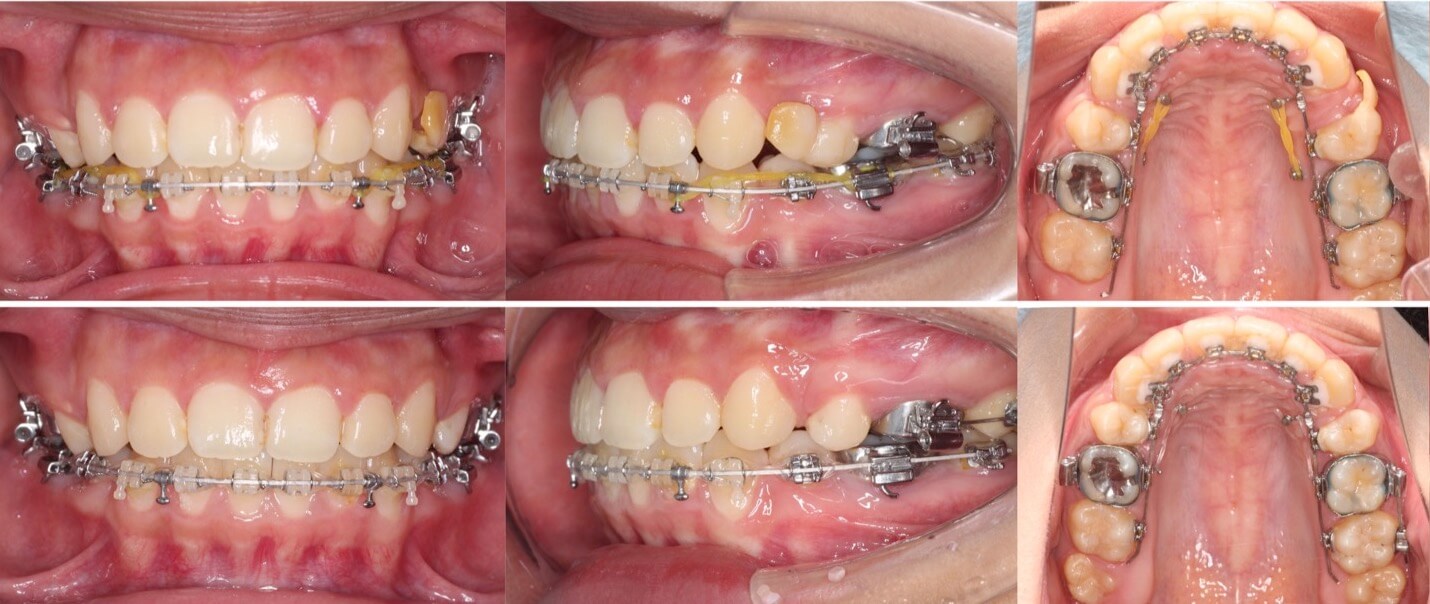

「前歯の角度が変化」

20代女性・ハーフリンガル装置・下あご後退型

前歯が前に傾斜している(倒れている)上下顎前突症例です。抜歯スペースに前歯を押し込むだけで、口元の突出が改善できる割と単純なケースになります。治療後は上下の前歯の角度も内向きに変わりました。

<症例概要>

主訴:前歯を引っ込めたい

年齢・性別:20代女性

住まい:千葉県佐倉市

症状:下顎後退・上下顎前歯唇側傾斜

治療方針:抜歯空隙の閉鎖(最大固定)

治療装置:ハーフリンガル矯正装置(上のみ裏側装置)

固定:歯科矯正用アンカースクリュー(口蓋側壁x2)

抜歯:上下第一小臼歯

治療期間:1年10か月

リテーナー:上下プレートタイプ+クリアタタイプ+フィックスタイプ

治療費用:1,4950,000(税込)

代表的副作用:痛み・治療後の後戻り・歯根吸収・歯髄壊死・歯肉退縮